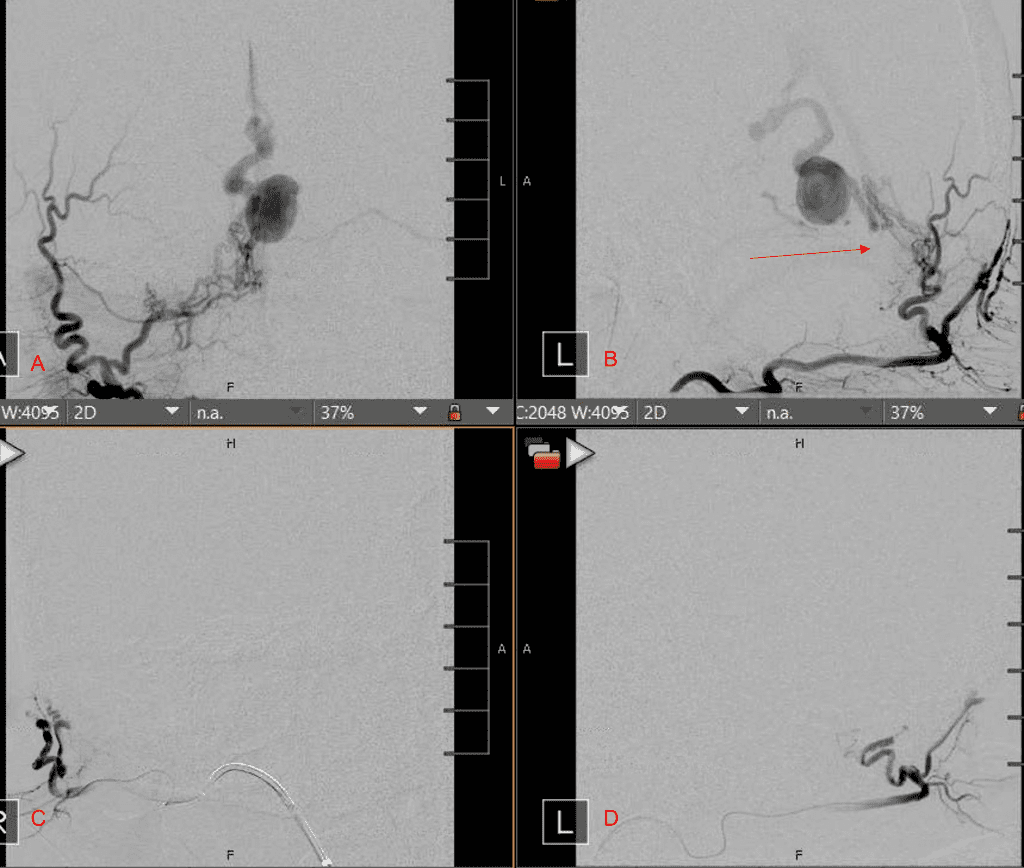

Figure 3. Right ECA AP and Lateral angiograms Pre (A and B) and Post NBCA embolization (C and D) Demonstrate near complete obliteration of right Occipital and Middle Meningeal Artery Fistulas

Figure 4. Left ECA AP and Lateral angiograms Pre (A and B) and Post NBCA embolization (C and D) Demonstrate near complete obliteration of Left Occipital Artery Fistulas.